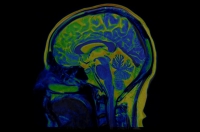

To investigate the neurobiological mechanisms of hallucinations and delusions within the framework of the hierarchical model, the researchers used functional magnetic resonance imaging to measure intrinsic neural timescales throughout the brain. These neural timescales reflect how long information is integrated in a given brain region. Most importantly, these neural timescales are organized hierarchically, making it a fitting measure to test the hierarchical model of psychosis.

The researchers collected data from 127 patients with schizophrenia from various online databases and determined how an individual’s neural timescales related to their hallucination and delusion severities together. They found that neural timescales in the lower levels of the hierarchy tended to be longer in patients with more severe hallucinations, while neural timescales in the higher levels tended to be longer in patients with more severe delusions. These results provide the first direct evidence of a potential neurobiological mechanism for hallucinations and delusions that fits within the hierarchical model of psychosis and can explain their clinical presentation. The common neurobiological mechanism for both symptoms could result in increased neural timescales, but the symptom-specific pathways are the level of the hierarchy at which the neural timescales are increased. “Our findings open the door for the development of treatments to target specific symptoms of psychosis depending on an individual subject’s symptom profile, in line with the current push for individualized medicine,” says Horga.